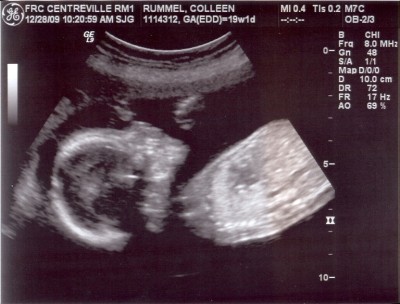

*pay no attention to the negligent mother hiding behind the computer screen*

I really and truly have been meaning to post these. But I really and truly did have an issue with my scanner. I would attempt to scan the images and it would say “uh, I’m sorry, which computer would you like these sent to?” and I’d remind it nicely that it would be for my cute little laptop. Then the scanner was all “whatever,” and wouldn’t send the images to my laptop. So I tried to dupe it by triggering the scanner remotely from my laptop (instead of the scanner itself), and I’ll be darned if the thing didn’t holler out at me “B**** please! I can see you in there!” and wouldn’t send me the images. So I was forced to ask Justin a few times to scan the sonogram images for me. I think I literally heard the scanner purr “oh, the Apple wants some images scanned? Sure! Whatever you want, sweetie!”

So cute. And if you have to ask what he’s doing back there, you probably don’t want to know.

So adorable! I can’t wait to see what this baby boy looks like on the outside!